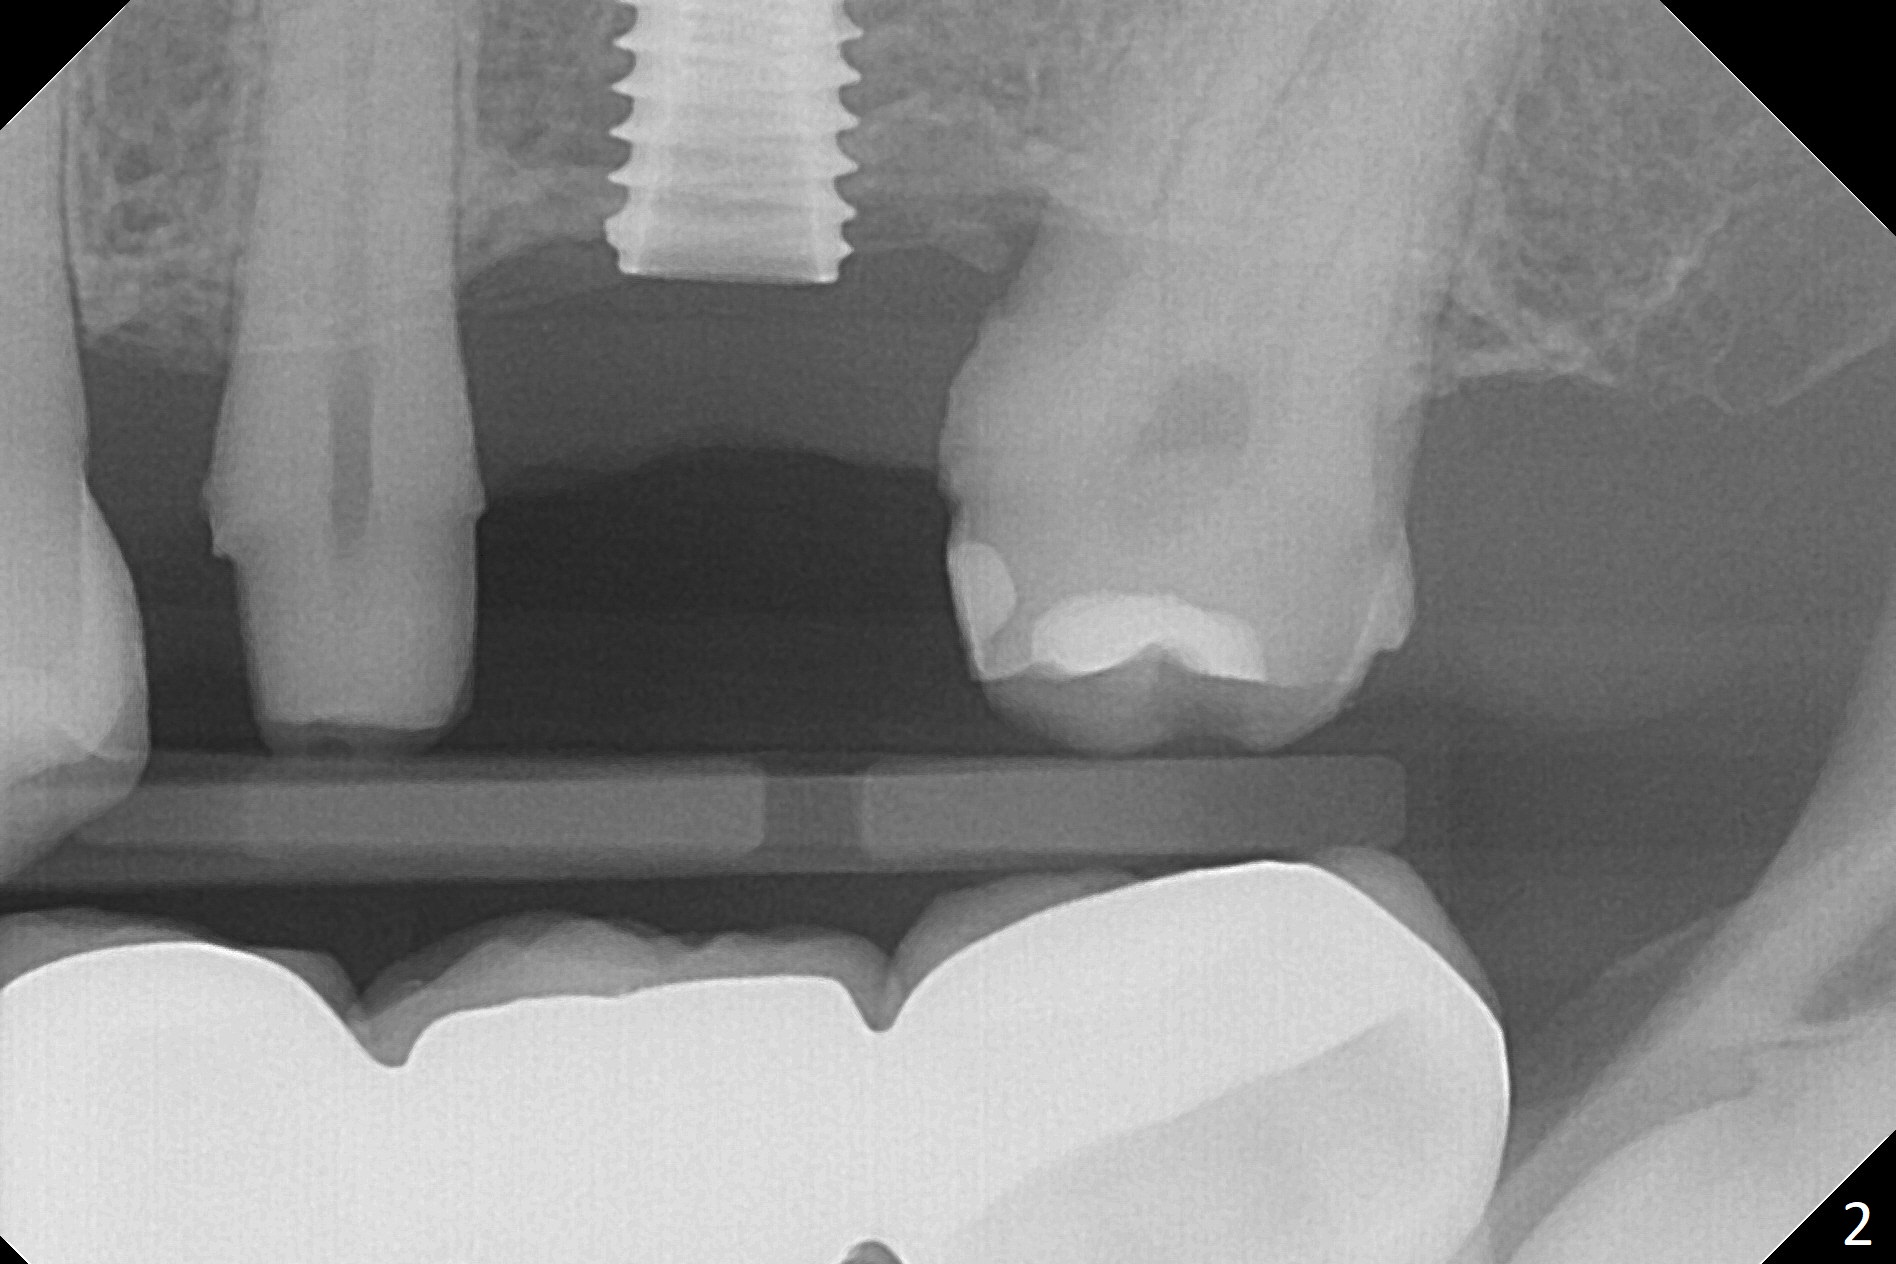

#13-15 FPD has not been used properly because of discomfort for 2 years. Before its removal, the discomfort derives from probing of the distal of #13 and mesial of #15, corresponding to calculus in the proximal areas. SRP is performed in UL quadrant after FPD removal. Bone density at the crest of the edentulous area is normal, while that of the medulla is low. After determination of trajectory and depth of initial osteotomy (Fig.1 (5 mm straight incision)), the site is underprep for a 4.5x13 mm Implant. Following adjustment, the implant is placed slightly subcrestal (Fig.2,3). It is possible that the discomfort of the previous FPD is due to overload, as suggested by the prominent buccal plate at #13 and 15, as compared to that of #12 (Fig.4 (5.2x4.5(3) mm cementation abutment at #14). Postop follow up shows that the tooth #15 may need RCT. The implant seems to enter the sinus (Fig.5 (2.5 months postop)) and be ready for restoration 3.5 months postop (Fig.6).